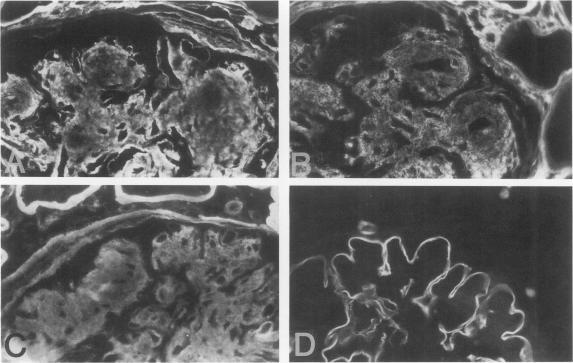

Diabetic nephropathy is characterized by progressive expansion of mesangial matrix and thickening of the glomerular basement membrane (GBM). Kidney tissues from 13 patients with insulin-dependent diabetes mellitus were studied by immunohistochemical techniques for the distribution of three recently described collagen peptides (M28+, M28 [Good-pasture antigen], and Alport antigen) and various components of classical type IV collagen [alpha 1(IV) noncollagenous (NC) globular domain, alpha 2(IV) NC, 7S, triple helix]. Recently M28 and M28+ were designated as NC monomers of alpha 3(IV) and alpha 4(IV) based on limited amino acid sequencing. During the course of the disease, the distribution of the M28 chains and the Alport peptide segregated completely from that of classical type IV collagen. In diabetic kidneys, antibodies to the M28 and Alport peptides reacted intensely with the thickened GBM but not with the mesangium. In contrast, the reactivity of antibodies to various components of classical type IV collagen was prominent within the expanded mesangial matrix with significant decrease in reactivity in the peripheral capillary wall. In hyalinized glomeruli, components of classical type IV collagen virtually disappeared, whereas the M28 and Alport peptides persisted in the collapsed GBM. These studies support the view that expansion of the mesangial matrix and thickening of the GBM involve separate and distinct collagen components. The differential expression of the M28 and Alport peptides compared with that of classical type IV collagen may be a consequence of differing sites of synthesis (classical type IV collagen from endothelial/mesangial cells and M28 and Alport chains from visceral epithelial cells), independent control mechanisms, and/or differences in degradation.

糖尿病肾病的特征是系膜基质进行性扩张和肾小球基底膜(GBM)增厚。采用免疫组织化学技术,对13例胰岛素依赖型糖尿病患者的肾组织进行研究,观察三种最近描述的胶原肽(M28 +、M28[古德帕斯丘抗原]和奥尔波特抗原)以及经典IV型胶原的各种成分[α1(IV)非胶原(NC)球状结构域、α2(IV) NC、7S、三螺旋]的分布情况。最近,基于有限的氨基酸测序,M28和M28 +被指定为α3(IV)和α4(IV)的NC单体。在疾病过程中,M28链和奥尔波特肽的分布与经典IV型胶原的分布完全分离。在糖尿病肾中,针对M28和奥尔波特肽的抗体与增厚的GBM强烈反应,但与系膜无反应。相反,针对经典IV型胶原各种成分的抗体反应在扩张的系膜基质中很突出,而在外周毛细血管壁中的反应性显著降低。在玻璃样变的肾小球中,经典IV型胶原成分几乎消失,而M28和奥尔波特肽仍存在于塌陷的GBM中。这些研究支持这样一种观点,即系膜基质的扩张和GBM的增厚涉及不同的胶原成分。与经典IV型胶原相比,M28和奥尔波特肽的差异表达可能是由于合成部位不同(经典IV型胶原由内皮/系膜细胞合成,M28和奥尔波特链由脏层上皮细胞合成)、独立的控制机制和/或降解差异所致。